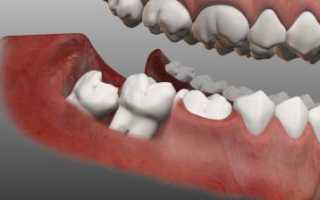

Последствия удаления ретинированного зуба мудрости

Если зуб мудрости прорезался не полностью, или его положение неверно по отношению к другим зубам (восьмёрка может расти в щёку или в соседний зуб), его называют ретинированным зубом. В таком случае операция по удалению может оказаться особенно сложной, и иметь неприятные последствия:

Фото 4. На фото видно, что нижние зубы мудрости растут в неправильном положении, в такой ситуации один из резцов ушел внутрь челюсти.